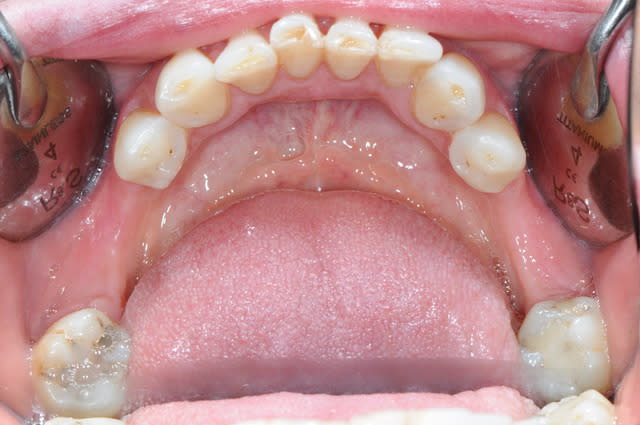

CAS 1

demande de restauration avec implant, mais, ne veut pas entendre parler de greffes et greffons.

la ROG lui semble plus "naturel".

1-2-3 situation de départ